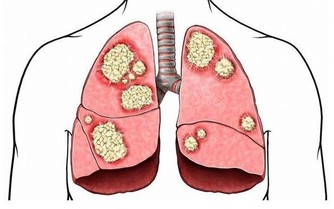

另外由於黃秋葵富含有鋅和硒等微量元素,能增強人體防癌抗癌。

8、預防大腸癌:富含水溶性膳食纖維,能保護腸胃,「預防大腸癌」。